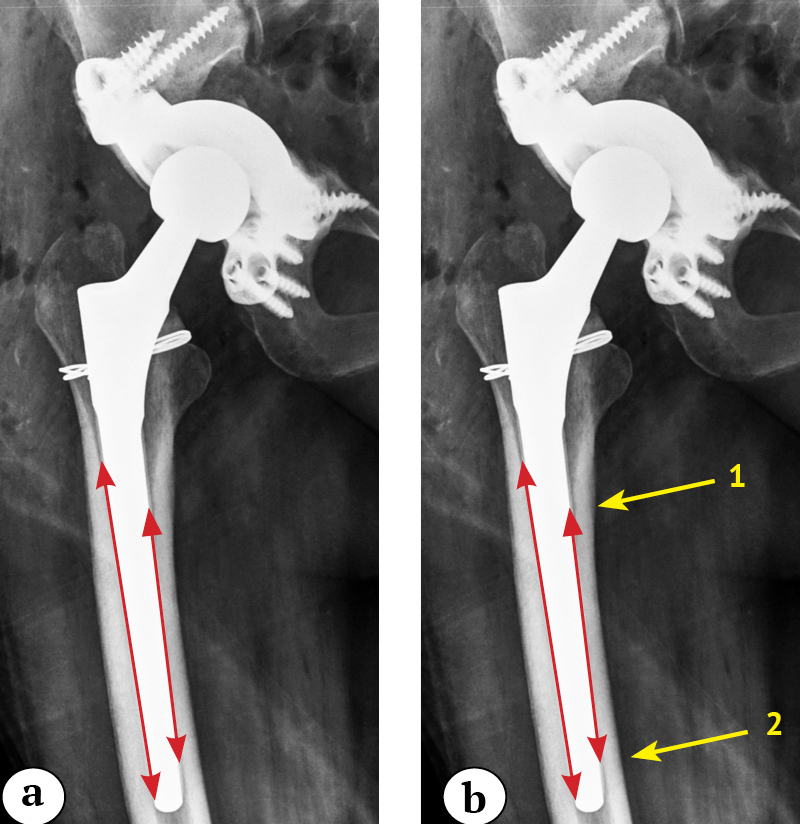

Radiological assessment was used to compare the position of the components at two time points: immediately after surgery and at the time of the last radiological examination. Stem subsidence was determined by comparing landmarks on the femur and on the prosthesis, which were clearly visible in all X-rays. The medial point of the lesser trochanter, calcar, proximal or distal contour of the lesser trochanter, and cerclage wires were used as landmarks on the femur. The apex of the stem shoulder was used as a landmark on the prosthesis. We drew a line from the reference point on the femur to the reference point on the prosthesis. This vertical line allowed us to calculate the actual length of the stem subsidence over the cortical bone (Fig. 1).

Fig. 1. X-ray images of the left hip of a 64-year-old patient after revision surgery: a — on day 1; b — in 9 months: 24.3 mm subsidence of the stem is observed